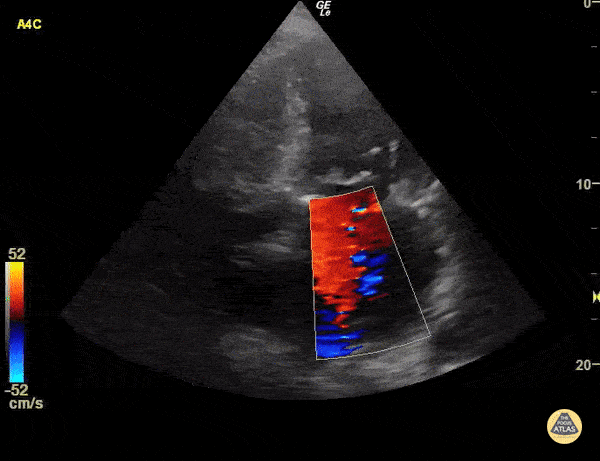

Moderate mitral regurgitation Sukh Singh, MD

https://www.thepocusatlas.com/valvulopathy